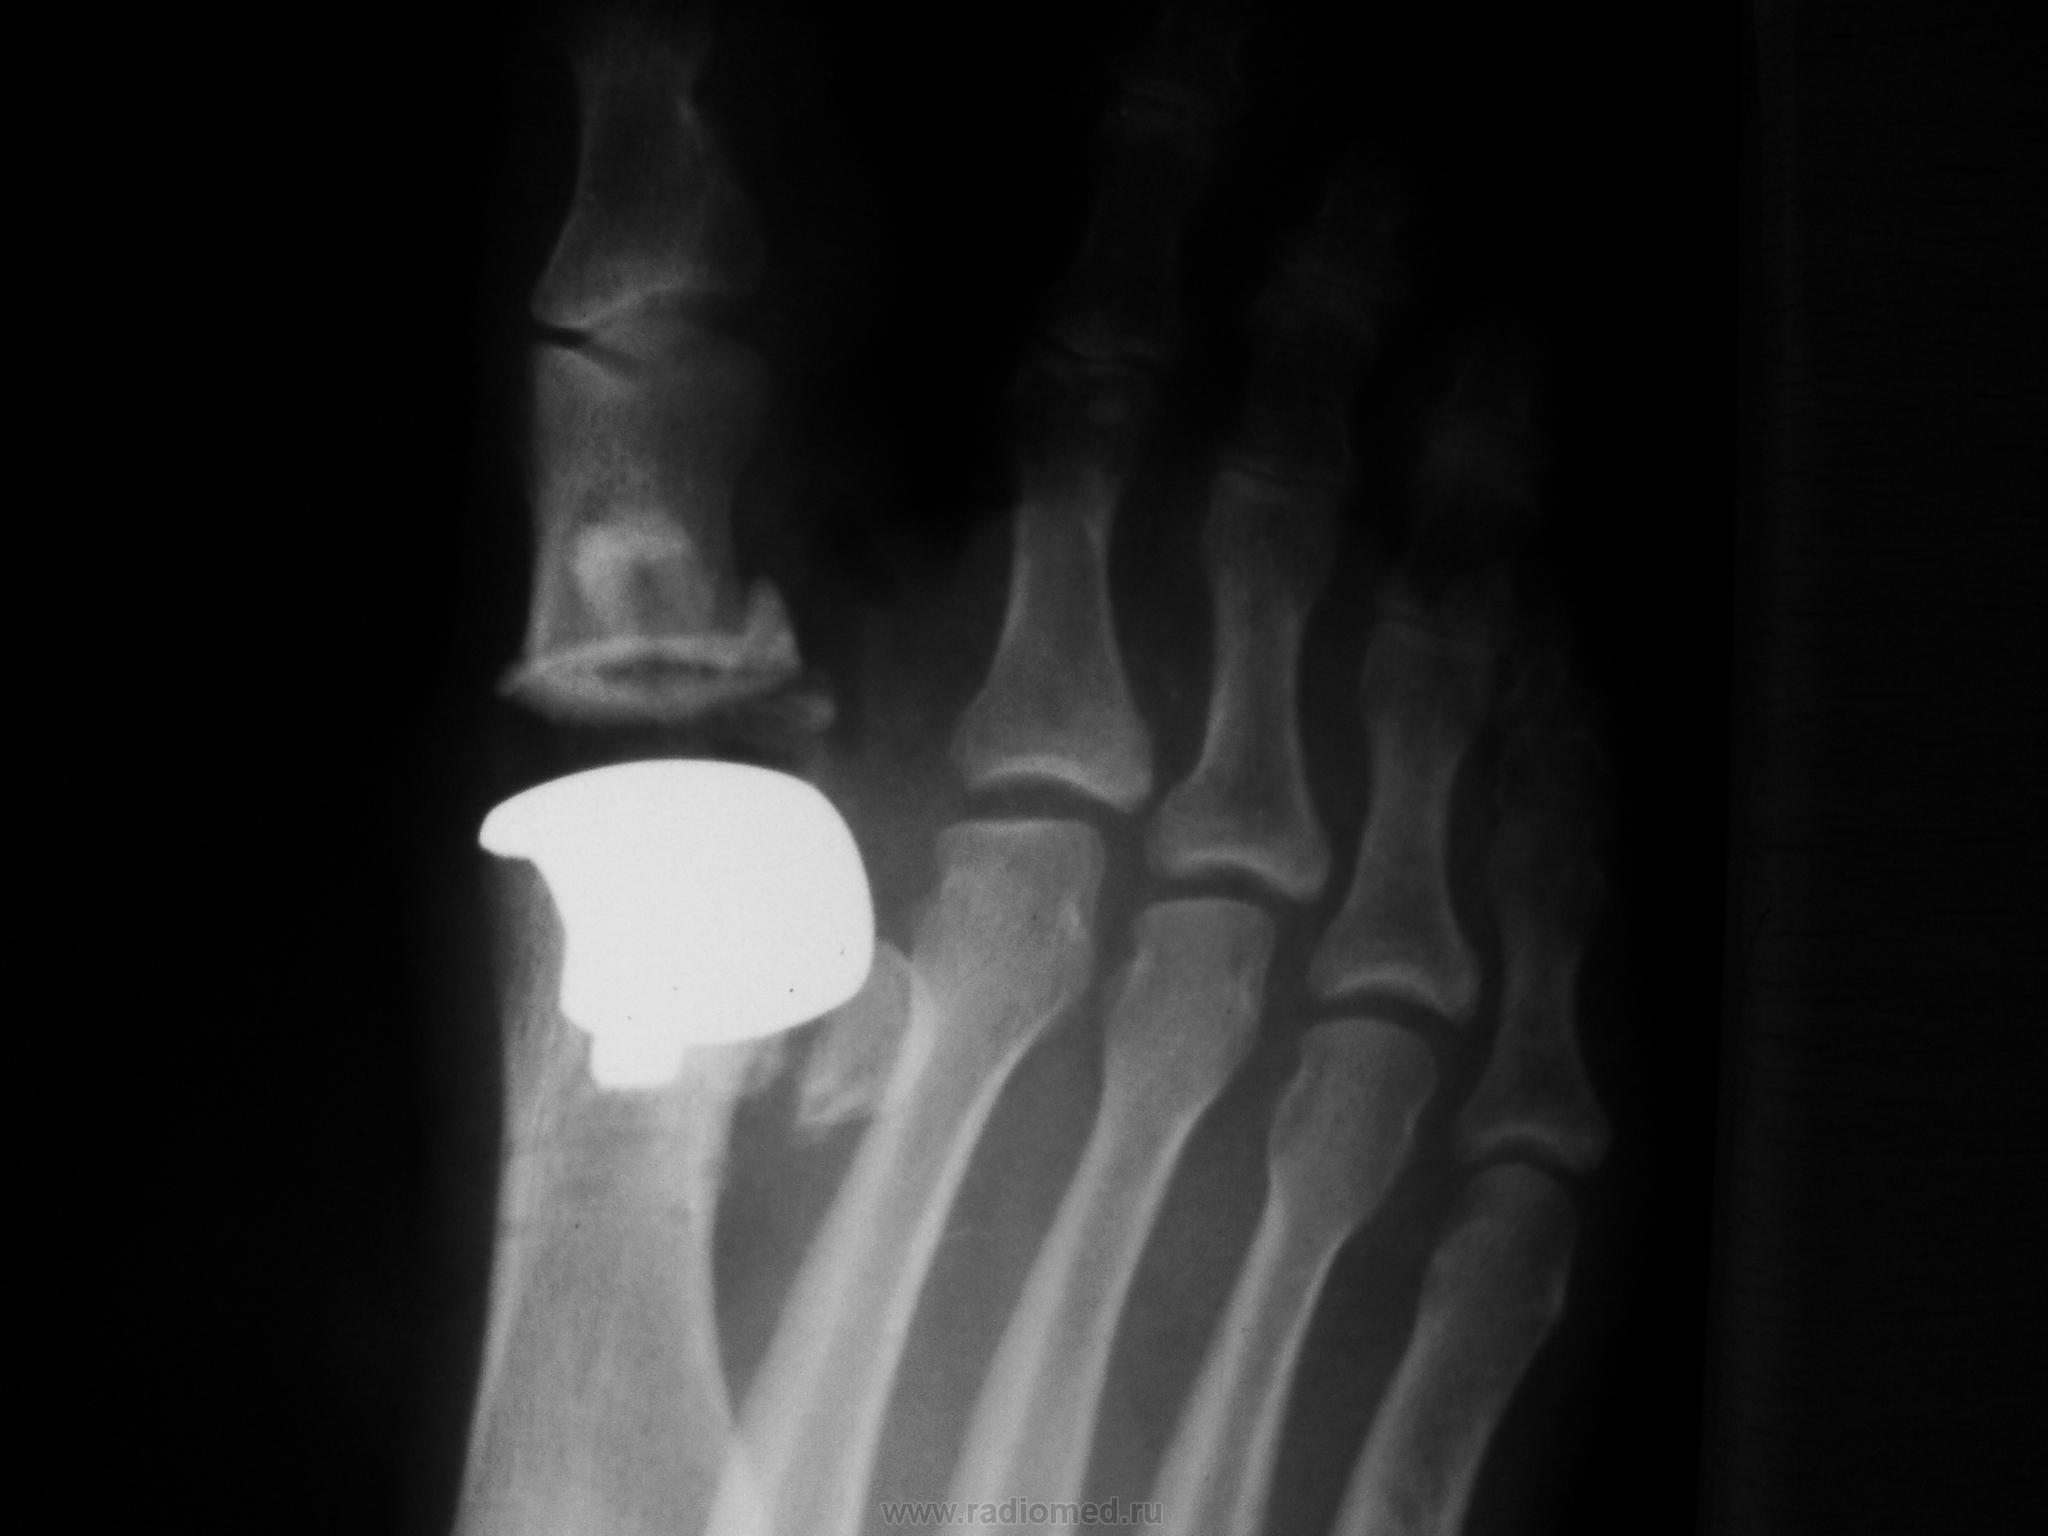

Один из методов лечения поперечного палоскостопия с выраженым дефартрозом 1 пл-ф суст. Операция Вредена-Мейо+ операция Брандеса+формирование поперечной связки стопы+протезирование. Померяйте какой сейчас Hallux valgus, опишите состояние культи и протеза.